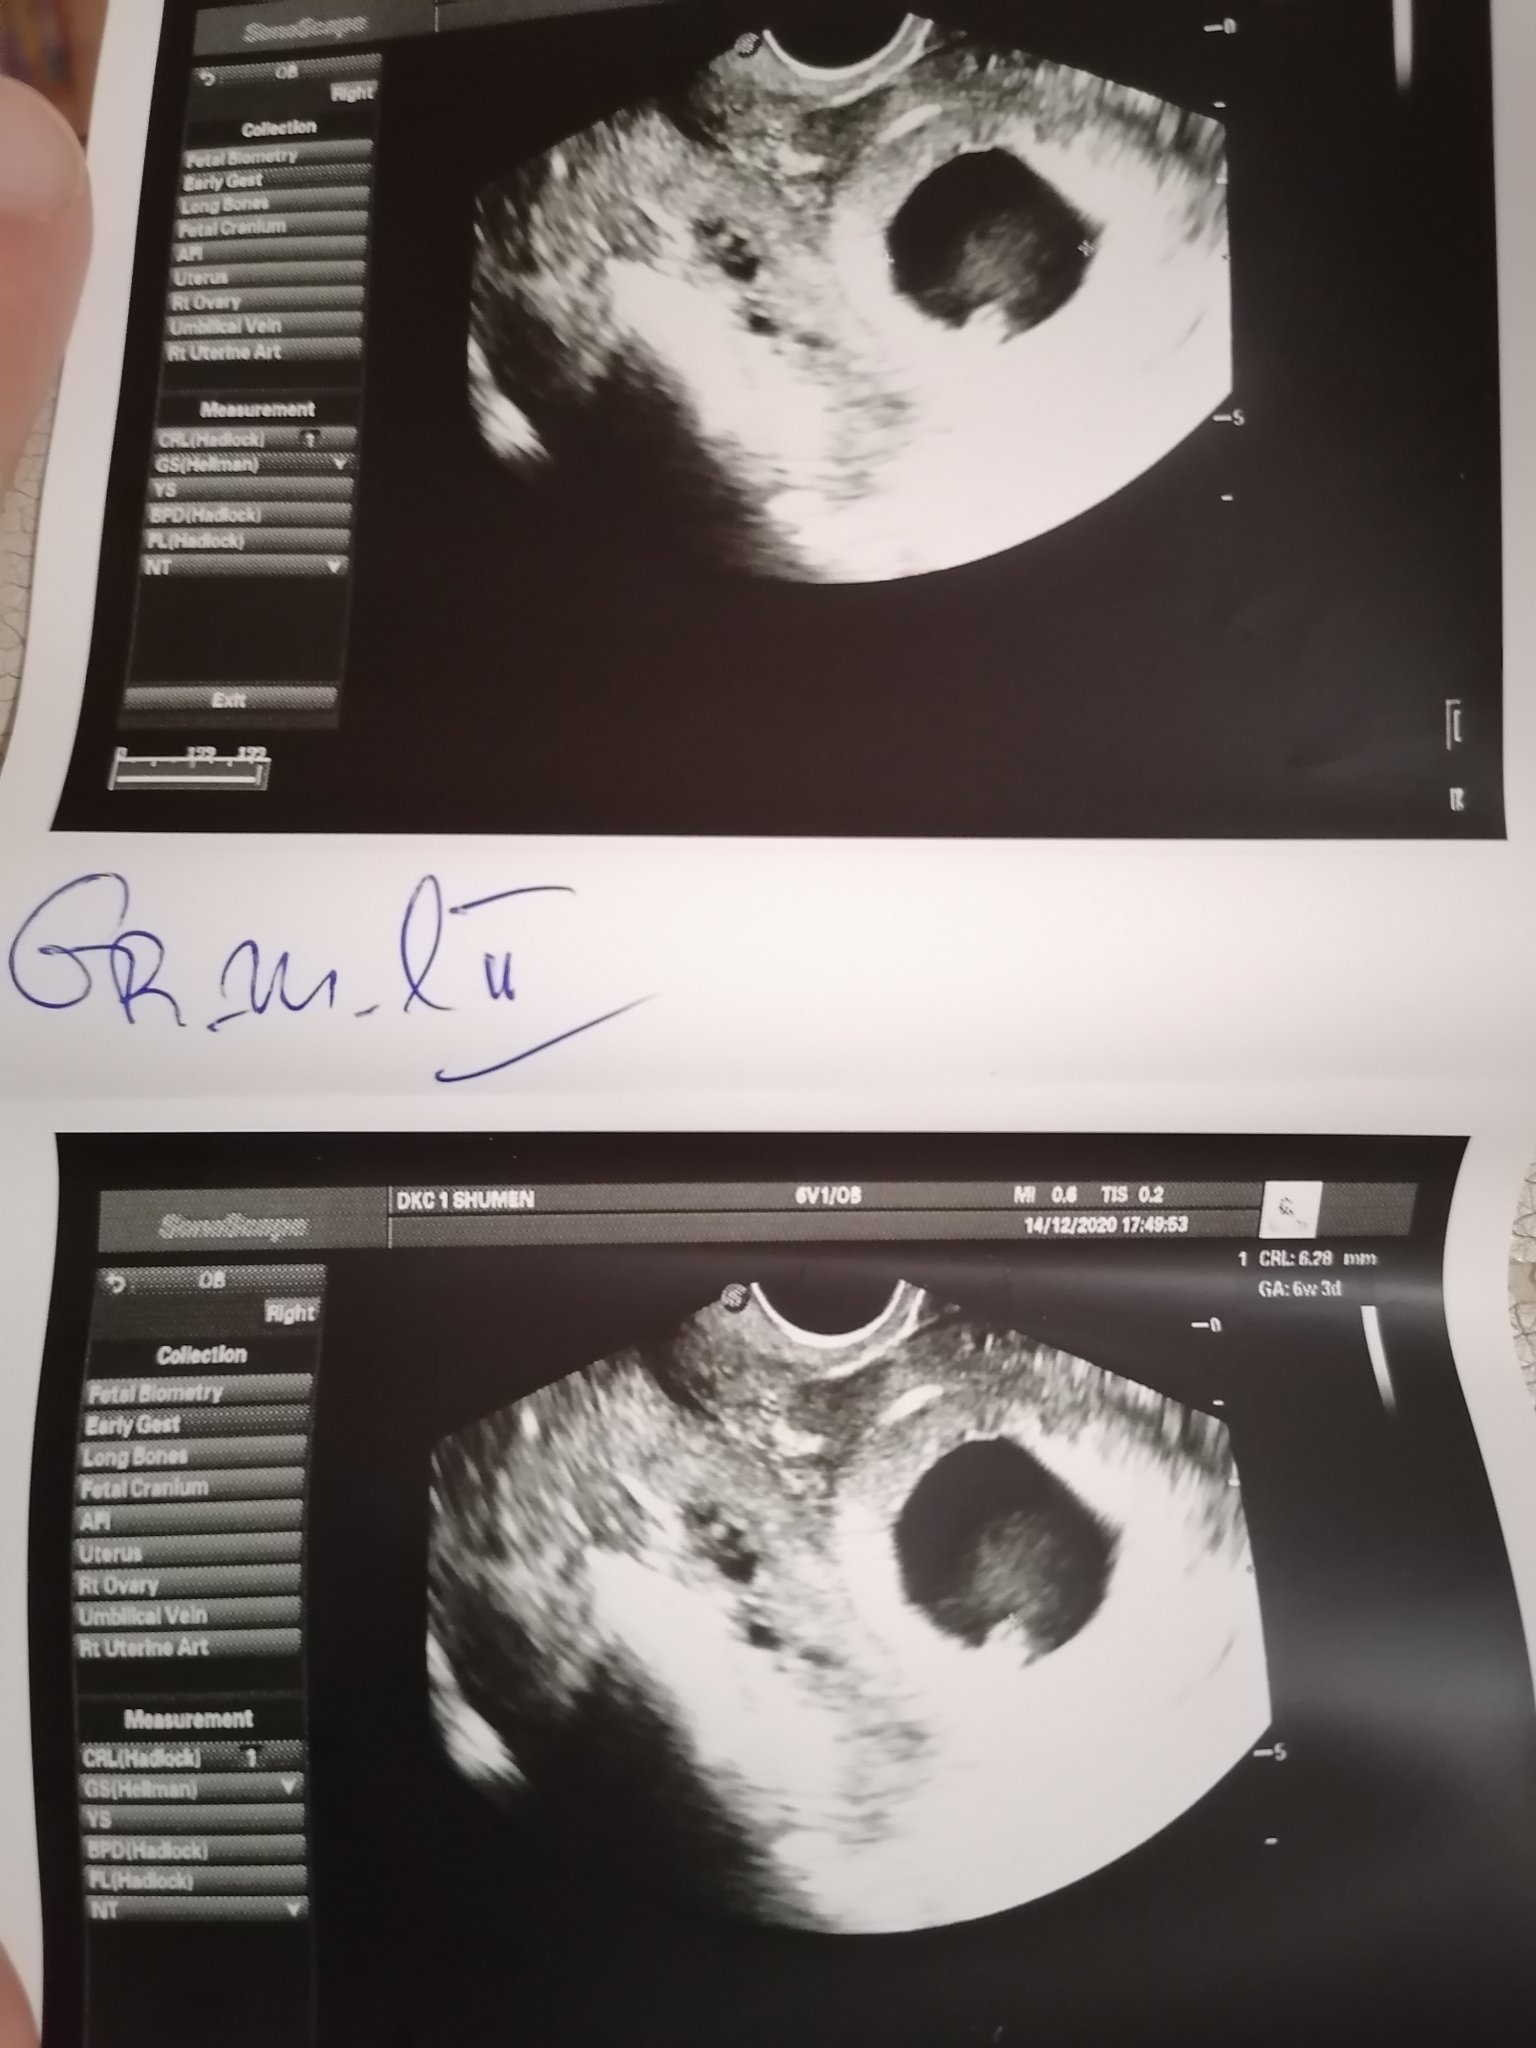

Здравейте. Имам установена бременност бях на втори преглед но съм доста объркана от това което ми каза докторката. Последната ми менструация е на 02.11.2020 днес на прегледа лекарката каза че плодния сак е по-голям  отговаря на 7с4д а ембриона на 6с4д една седмица разлика,но в действителност според датана на менструацията ембриона си отговаря трябва да съм в 6 седмица. Незнам какво да мисля имах кървене преди една седмица незнам дали има общо.Според АГ-то

има шанс за нормална бременност но това разминаване я притеснявало.Ще прикача снимки ако някой има мнение ще съм благодарна🙂

Ходихте ли отново, какво ви казаха? Гледам има сърдечна дейност, защо пък да е притеснително, при мен на първия преглед вървеше със седмица назад, на втория преглед си беше само с ден назад, надявам се да имате само хубави новини Simple Smile и на мен ми казаха, че плодния сак е по уголемен, но това не било проблем